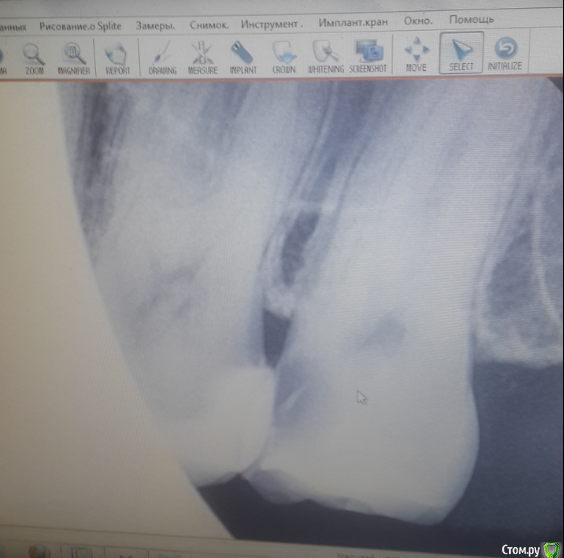

umka82 Опубликовано 26 мая, 2016 Поделиться Опубликовано 26 мая, 2016 Здравствуйте, уважаемые доктора! Очень нужен ваш профессиональный взгляд/совет на тему запущенного кариеса. Посещение стоматолога по ДМС принесло мне неприятные сюрпризы- один из которых уже весьма запущенный и требующий лечения межзубный (если правильно употребляю -дистальный) кариес 27 зуба (верхний слева). Зуб не болит и никакого дискомфорта не чувствую.Стоматолог мне объяснила, что по ДМС такое лечение не производится, а надо мне не больше-не меньше ставить коронку. После этого, по другим причинам, я посещала своего стоматолога-пародонтолога, которая не увидела в моем случае криминала (равно как и оснований ставить коронку) и рекомендовала 2х ортопедов для консультации.Первый врач порекомендовал просто пролечить каналы и поставить пломбу. Второй уже более масштабно оценил мои зубы и было рекомендовано керамические вкладки на 8 зубов (6 и 7-ки): при этом также не увидел большой беды, объяснил что именно этот зуб не особо участвует в жевании и при отсутствии средств на вкладки на все 8 предложил его также просто запломбировать (предварительно пролечив каналы) и ставить вкладки только на 6ые. Я очень не хочу терять свой зуб, пусть даже может и не такой важный. Больше всего опасаюсь варианта, когда зуб потом расколется при жевании от обширной пломбы (т.к. сам зуб уже с пломбирован по всей нижней поверхности). Слышала, что в этом случае спасти его не удастся. Вопрос: какой метод лечения вы считаете более подходящей в данном случае?оправдана ли пломбировка зуба ? Является ли керамическая вкладка более надежным в сравнении с пломбой вариантом? Прошу прощения за качество фото, разрешили только такой снимок сделать. Ссылка на комментарий